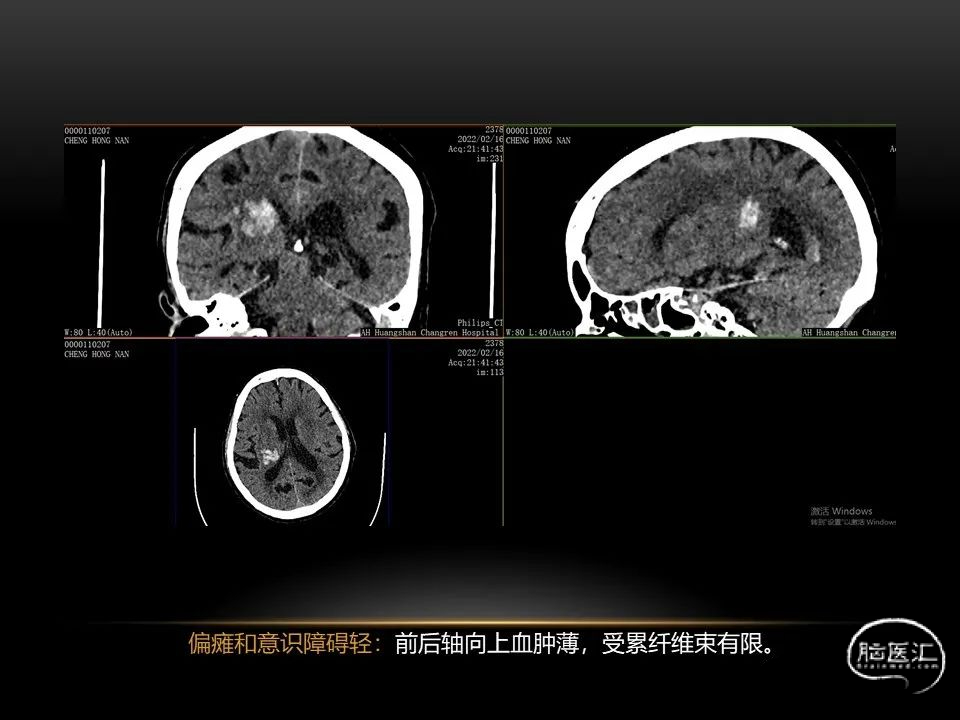

自发性脑出血临床上很常见,不同原因有特征性的出血部位。例如:基底节出血和丘脑出血大多是高血压性脑出血;脑叶出血,特别是多次复发的脑叶出血多见于老年人的脑血管淀粉样变。

自发性脑出血不仅仅累及内囊后肢才会出现偏瘫及偏身感觉障碍,病变累及大脑脚或辐射冠同样有可能有类似症状和体征。内囊、辐射冠、大脑脚等结构之间是延续的,只是不同区域不同名称而已。定位诊断需要对解剖结构概念清晰,读片准确辨认,灵活掌握。